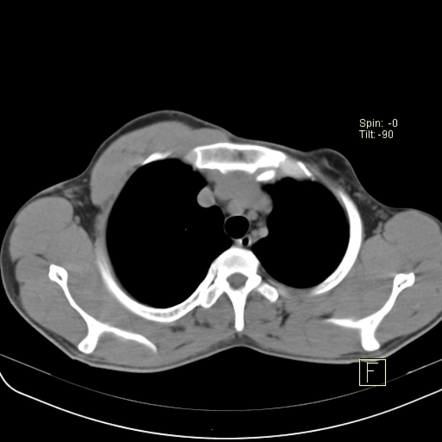

Poland’s Syndrome-CT - Sumer’s Radiology Blog

www.indianradiology.comsyndrome radiology

www.indianradiology.comsyndrome radiology